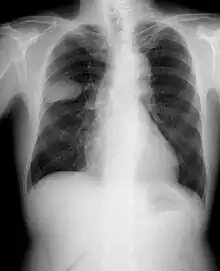

Radiografía simple de tórax

En las radiografías simples de tórax se puede observar alguna anormalidad en casi el 98 % de los pacientes con un carcinoma broncogénico, y el 85 % son imágenes sugestivas para sospechar el diagnóstico por las alteraciones pulmonares distales (atelectasia), la existencia de adenopatías (ensanchamiento mediastínico) o detección de invasión de la pared torácica. La radiografía de tórax detecta elementos sospechosos en la mayoría de los pacientes con tumores pulmonares.[133] No se recomiendan las tomas radiológicas en serie para la detección temprana del cáncer de pulmón.[121]